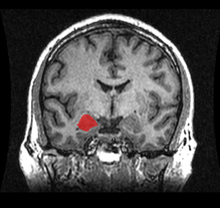

TLE is usually diagnosed in childhood or by the teenage years. Physicians diagnose TLE by taking a medical history, blood tests, and brain imaging (EEG, CT scan, PET, and/or MRI). It can have a number of causes such as head injury, stroke, brain infections, structural lesions in the brain, or brain tumors, or it can be idiopathic and have no apparent cause. The first line of treatment is through anticonvulsant medication. Surgery may be an option for some people, especially when there is an observable abnormality in the brain. Another treatment option is electrical stimulation of the brain through an implantation called the vagus nerve stimulation (VNS) device.[1]

After childhood onset, one third will "grow out" of TLE, finding a lasting remission up to an average of 20 years. The finding of a lesion such as hippocampal sclerosis (a scar in the hippocampus), tumour, or dysplasia, on magnetic resonance imaging (MRI) predicts the intractability of seizures.[53]